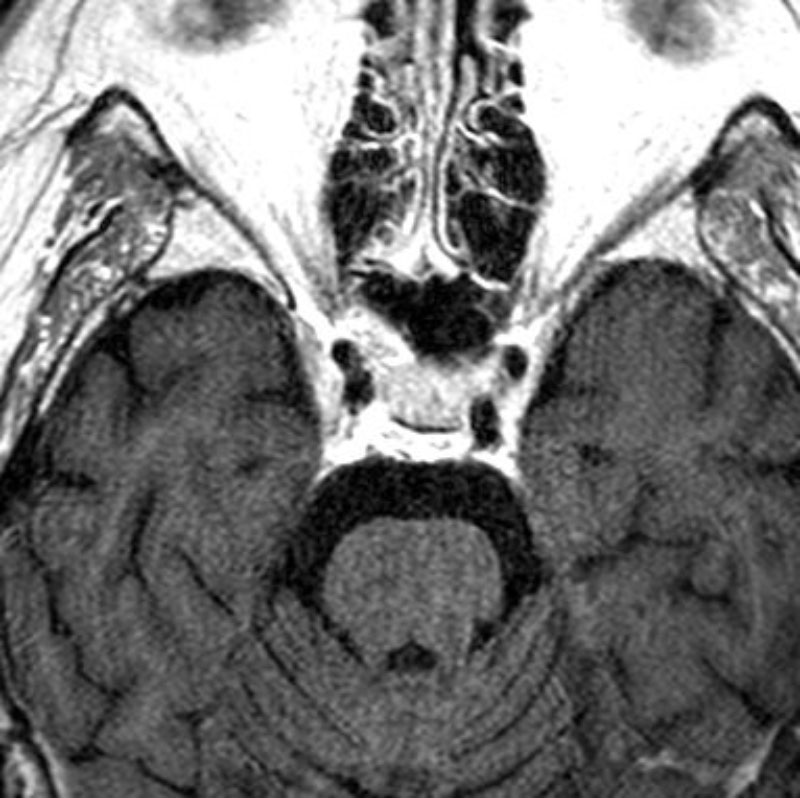

412

'23年5月

20代

小脳血管芽腫

頭蓋内腫瘍摘出術

No.’23_46 手術前1

No.’23_46 手術前2

No.’23_46 摘出 前

No.’23_46  摘出 中

No.’23_46 摘出 後